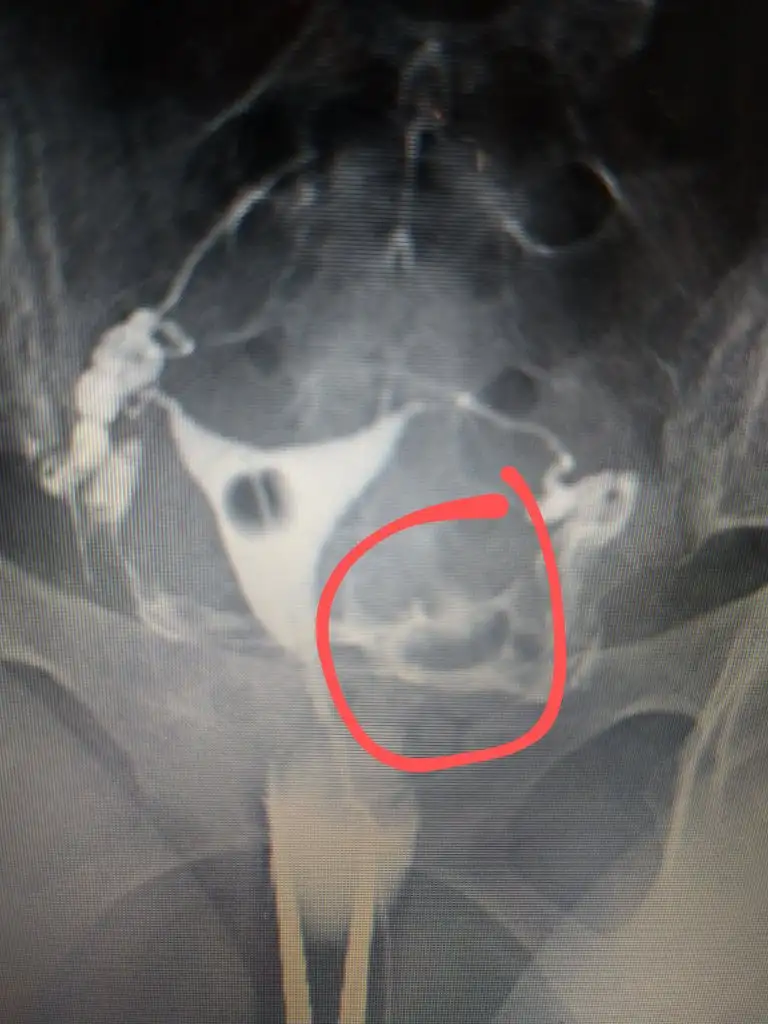

Onun hatlar karışık biraz. Çekim sonrası radyologun mesai saati bittiği için rapor yetişmemiş. Pazartesi alacak sonucunu. Kendi doktoru tüplerden birinde tıkanıklık var gibi konuşmuş ama başka doktorlara da göstermiş, basınçla açılmış demişler